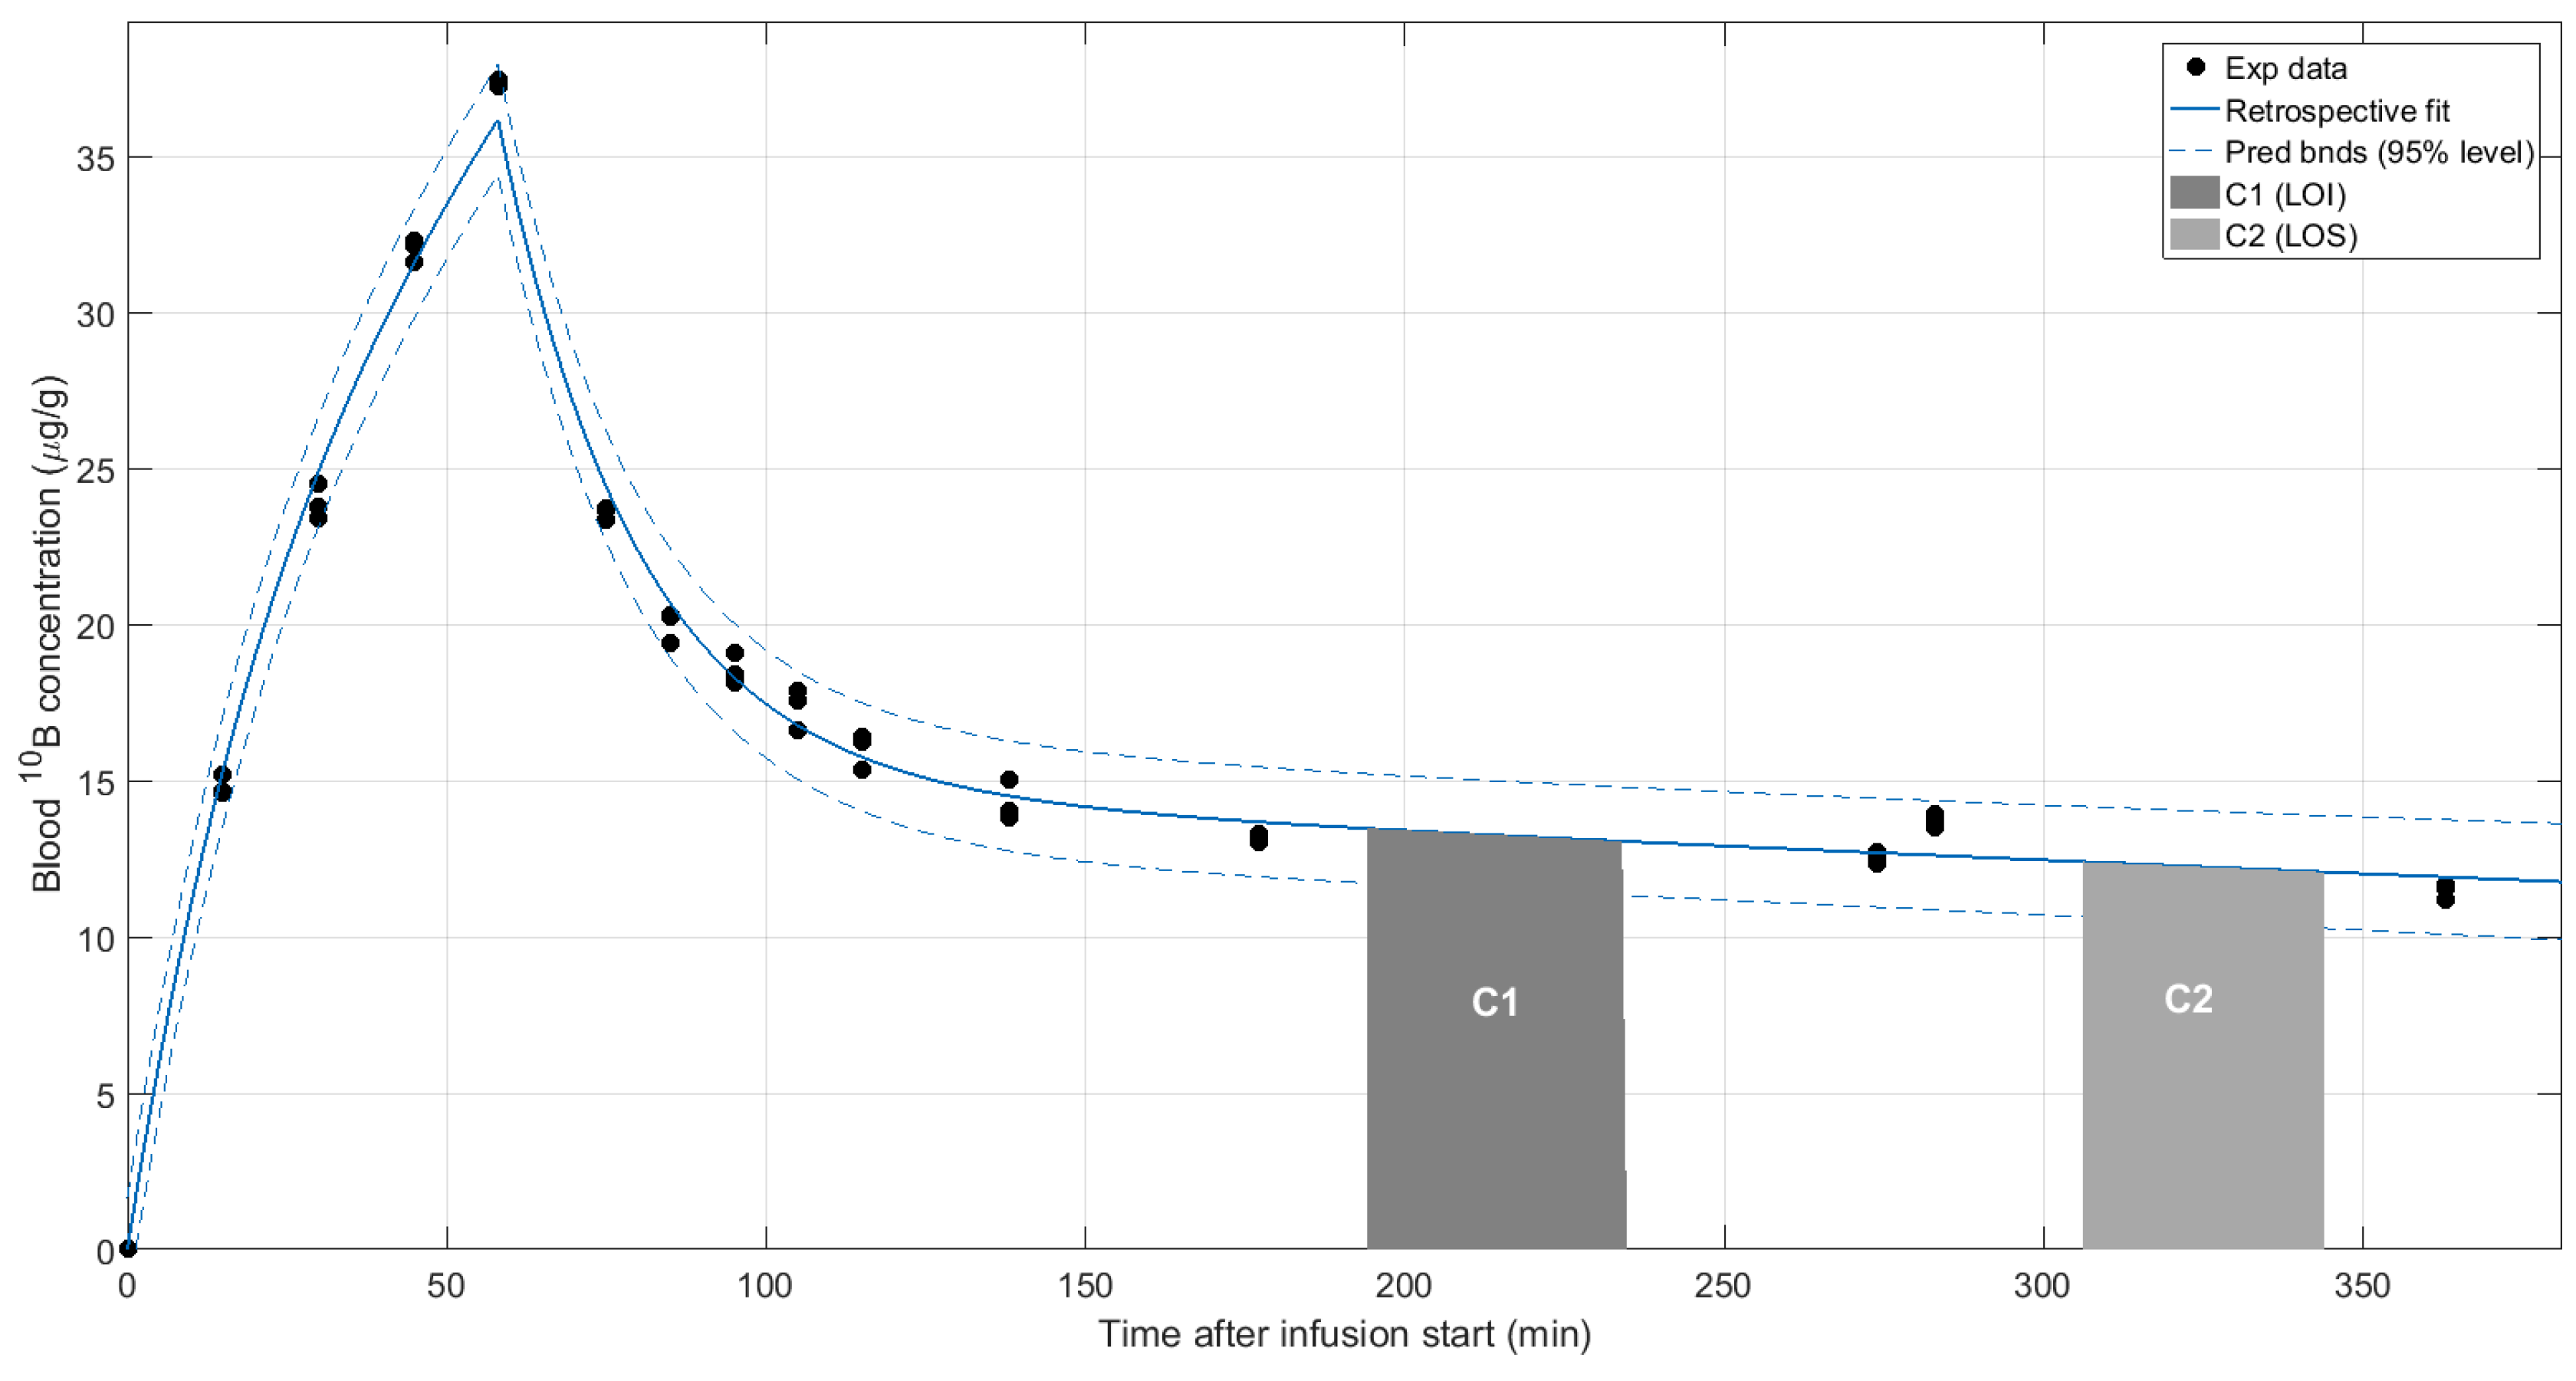

| Mixed-breed Lucy 12 years old | SCC nasal cavity and paranasal sinuses with bone destruction Pre-treatment TV: 51 cm3 Re-treatment Pre re-treatment TV: 77 cm3 | Chemo-therapy pre-BNCT | 2 appl., 3 weeks apart; 2 portals per appl. Re-treatment with full dose BNCT, 10 months after the first BNCT treatment, due to local tumor regrowth | Partial response (PR) TV 1 month post 1st treatment BNCT: 25 cm3 Cause of death: euthanasia due to recurrence and decline Survival post 1st treatment: 13.5 months Survival post re-treatment: 3 months | Mild nasal keratosis Mild mucositis Mild somnolence Re-treatment: Mild somnolence and eye irritation | Positive tumor response and clinical benefit For 8 months, optimum clinical signs and no protruding tumor mass. Re-treatment due to tumor regrowth at 10 months post 1st treatment Initial positive response, recurrence and decline 3 months after re-treatment |

| Alsatian Senshi 9–10 years old | Nasal chondrosarcoma TV: 105 cm3 | Chemo-therapy pre-BNCT | 2 appl., 3.5 weeks apart; 3 portals per appl. | PR TV 1 month post-BNCT: 57 cm3 Cause of death: euthanasia due to recurrence and decline Survival post BNCT: 10 months | Mild somnolence Mild–moderate nasal mucositis | Positive tumor response and clinical benefit |

| Labrador Mora I 9 years old | Oral amelanotic melanoma TV: 342 cm3 | 5 surgeries Immuno-therapy pre-BNCT | 2 appl., 5 weeks apart; 2 portals/appl. | PR TV 1 month post 1st appl.: 284 cm3 TV 2.5 months post 1st appl.: 149 cm3 Cause of death: Euthanasia due to lung metastasis diagnosed 2 months post BNCT Survival post 1st appl.: 2.5 months | Moderate mucositis | Positive tumor response and clinical benefit |

| Labrador Mora II 11 years old | Oral amelanotic melanoma TV: 12 cm3 | Surgery pre-BNCT Immuno-therapy 10 weeks post BNCT when liver and lung metastases were diagnosed | 2 appl., 4.5 weeks apart; 2 portals per appl. | PR TV 1 month post 1st appl.: 2.9 cm3 TV 2 months post 1st appl.: 0.60 cm3 Cause of death: recurrence and lung metastasis Survival post BNCT: 1 year | Mild mucositis | Positive but short-term tumor response and clinical benefit |

| Labrador Jake 12 years old | Nasal SCC (poorly differentiated) Myasthenia TV: 29 cm3 | 1 surgery pre-BNCT Palliative chemo-therapy 7 months post BNCT, after regrowth | 2 appl., 4.5 weeks apart; 2 portals per appl. | PR as revealed by complete reduction in visible tumor volume and improvement in quality of life Cause of death: euthanasia due to recurrence and decline No CT scan 1 month post treatment Survival: 8.5 months post-BNCT | Moderate–severe mucositis that responded to medication | Positive tumor response and clinical benefit |